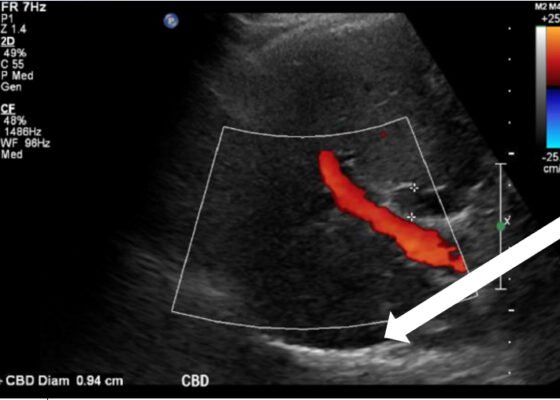

A Case Report on Detecting Porcelain Gallbladder form Wall-Echo-Shadow Sign on Point-of-Care Ultrasound

DOI: https://doi.org/10.21980/J8164GPoint-of-care ultrasound (POCUS) was performed by the emergency physician. Gallbladder ultrasound (US) should be performed using a curvilinear probe. If the patient’s body habitus does not allow for the use of a curvilinear probe, a phased array probe may be used. To find the gallbladder with ultrasonography, two approaches are commonly used. Many physicians prefer the “subcostal sweep” in which the probe is placed on the xiphoid process in a sagittal plane and swept along the inferior costal margin until the gallbladder is visualized. If this does not adequately locate the gallbladder, the “X minus 7” approach may be used. In this approach, the probe is placed on the xiphoid (X) process in a transverse view and moved 7 centimeters (minus 7) to the patient’s right. This technique is useful for patients with a larger body habitus. If the gallbladder is still not visualized, placing the patient in left lateral decubitus position or asking them to take a deep breath and hold may help the ultrasonographer locate the gallbladder. The US revealed mild hepatic biliary duct dilation with cholelithiasis and sludge, but no additional evidence to suggest cholecystitis. The US image showed a dilated common bile duct at 0.94 cm and calcifications. Visualization of the gallbladder wall is essential in differentiating between a positive wall-echo-shadow (WES) sign and a porcelain gallbladder. While a hypoechoic gallbladder wall is indicative of a WES sign, a hyperechoic wall layer will indicate a calcified gallbladder wall, suggesting a porcelain gallbladder. In image 1, the hyperechoic gallbladder wall can be visualized (white arrow), suggesting the presence of porcelain gallbladder and distinguishing it from a positive WES sign.